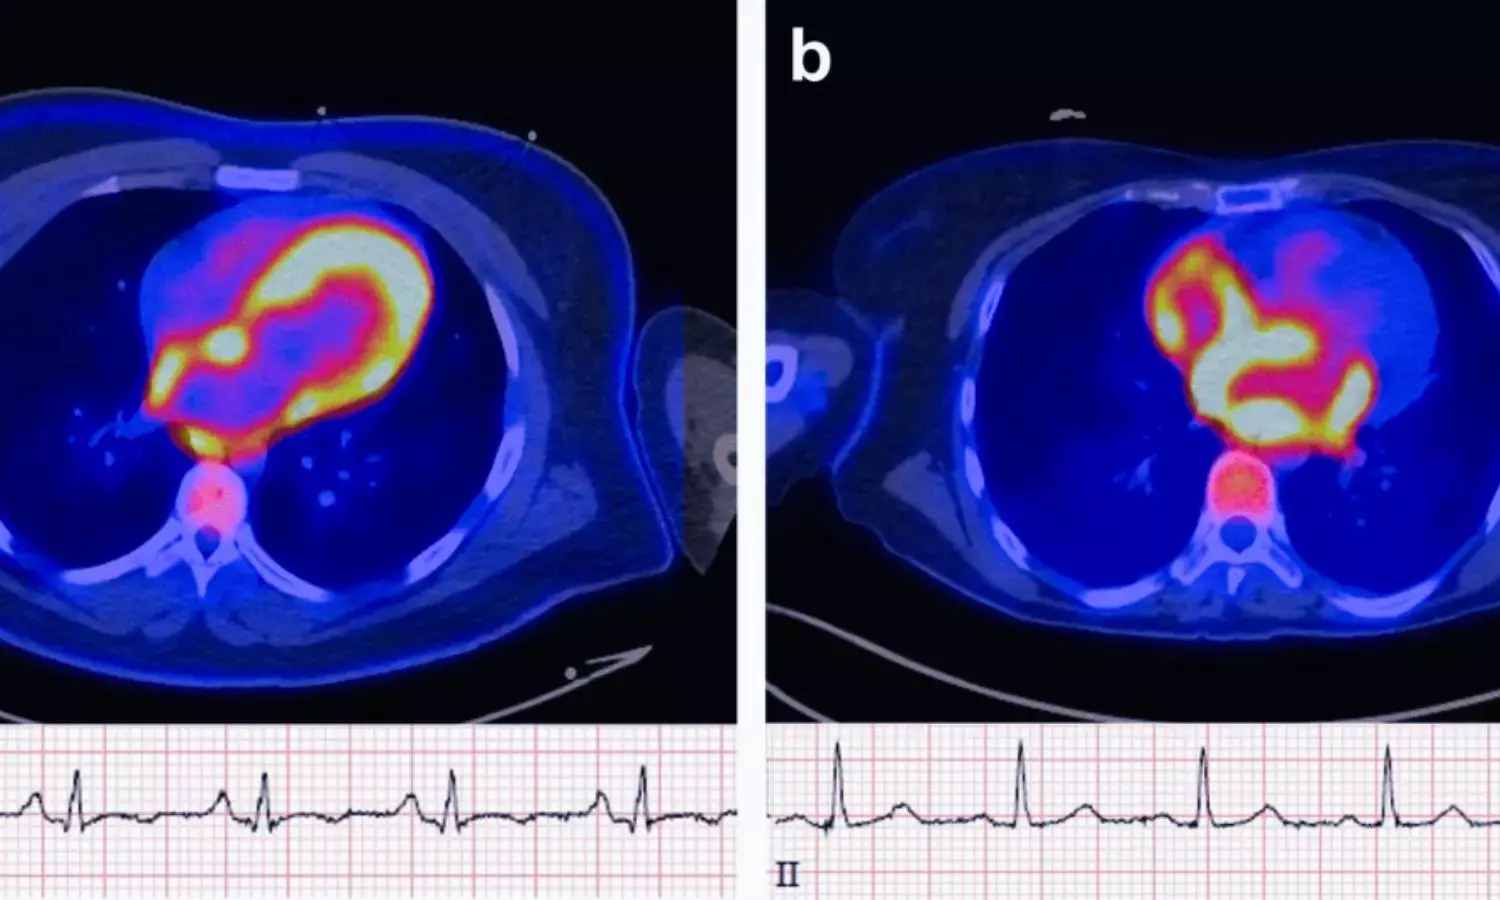

USA: Positron emission tomography (PET) imaging may help identify patients at higher risk of developing atrial fibrillation (AF) by detecting increased metabolic activity in the atrial walls, a new study published on January 20 in JACC: Advances has found. The findings suggest that atrial uptake of the F-18 fluorodeoxyglucose (FDG) radiotracer is associated with a significantly higher likelihood of incident AF over long-term follow-up.

PET images were evaluated using both visual and semiquantitative methods. Atrial FDG uptake was assessed based on intensity relative to background activity, while standardized uptake values and target-to-background ratios were calculated in areas of highest uptake.